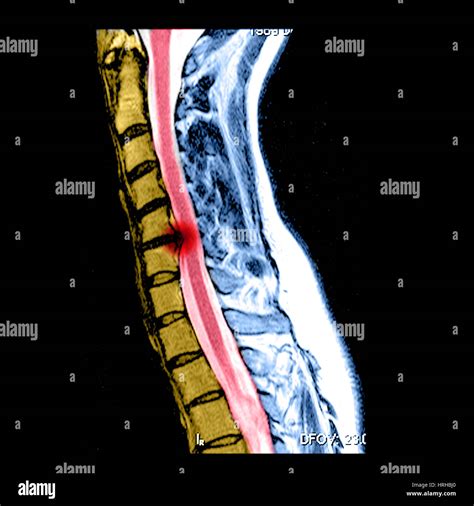

The cervical spine consists of seven vertebrae located in the neck. Between these vertebrae are intervertebral discs designed to provide flexibility and support. A slipped disc in neck occurs when the disc's protective outer ring—the annulus—weakens or tears, allowing the jelly-like center—the nucleus pulposus—to bulge out. This protrusion can compress the spinal cord or the nerve roots branching out from it.

MRI Scan Provides clear images of soft tissues, including discs and nerves.